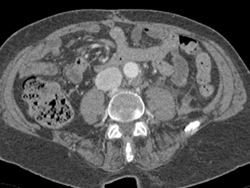

Psoas Abscess